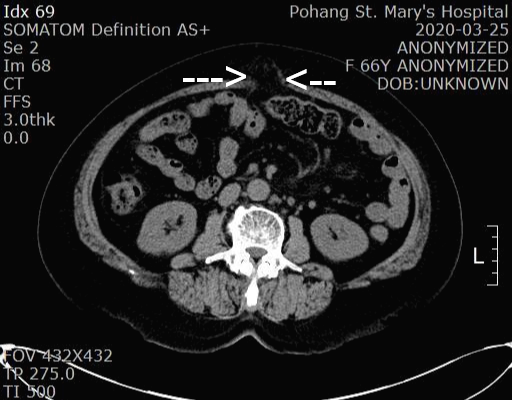

진찰 소견상 복벽에 힘을 줄때 튀어나오는 덩어리가 만져져서 복부 CT를 시행했습니다.

복부 CT에서 근막의 소실(화살표 사이)이 보이면서 복강내의 장간막이 복강 밖으로 빠져 나간 소견이 보입니다.